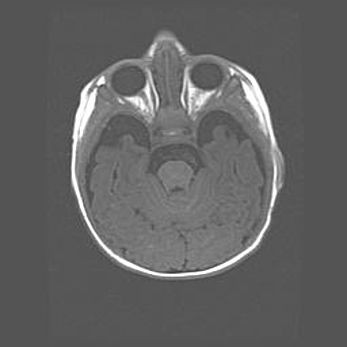

Наружная гидроцефалия с возможной атрофией височных областей.

Возраст: 28 дней

Вес: 3670 г

Пол: мужской

Окружность головы: 38 см

Срок гестации: 40 недель

Гидроцефалия головного мозга у новорожденных – это заболевание, которое характеризуется скоплением избыточного количества спинномозговой жидкости в желудочковой системе головного мозга в результате затруднения её перемещения от места выработки к месту поглощения в кровеносную систему или вследствие нарушения абсорбции. При открытой наружной форме гидроцефалии у новорожденных расширяются и переполняются субарахноидные пространства.

При нормотензивных  формах,  которые,  как  правило,  являются  следствием  перенесенных ишемических  повреждений  паренхимы  мозга,  возможно  сочетание микроцефалии  с нормотензивной гидроцефалией. В основе данных изменений лежит атрофия больших полушарий с преимущественной  локализацией  в  лобно-височных  областях.